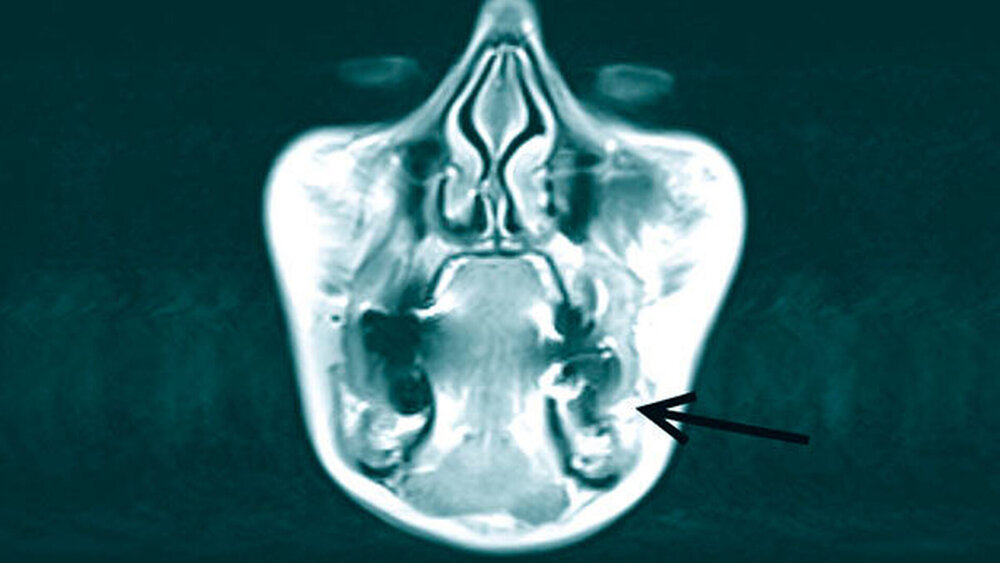

In der durchgeführten OPG-Aufnahme zeigte sich bei mäßiger Aufnahmequalität ein konservativ, prothetisch und chirurgisch versorgtes Restgebiss (Abbildung 1) ohne Aufhellungen oder Verschattungen. Nebenbefundlich fand sich ein impaktierter und dystoper Zahn 38. In der Sonografie zeigte sich eine 13 mm × 6 mm × 7 mm große, gut abgrenzbare Raumforderung ohne dorsale Schallverstärkung. Die Patientin wurde daraufhin zur weiteren Abklärung im Intervall stationär aufgenommen.